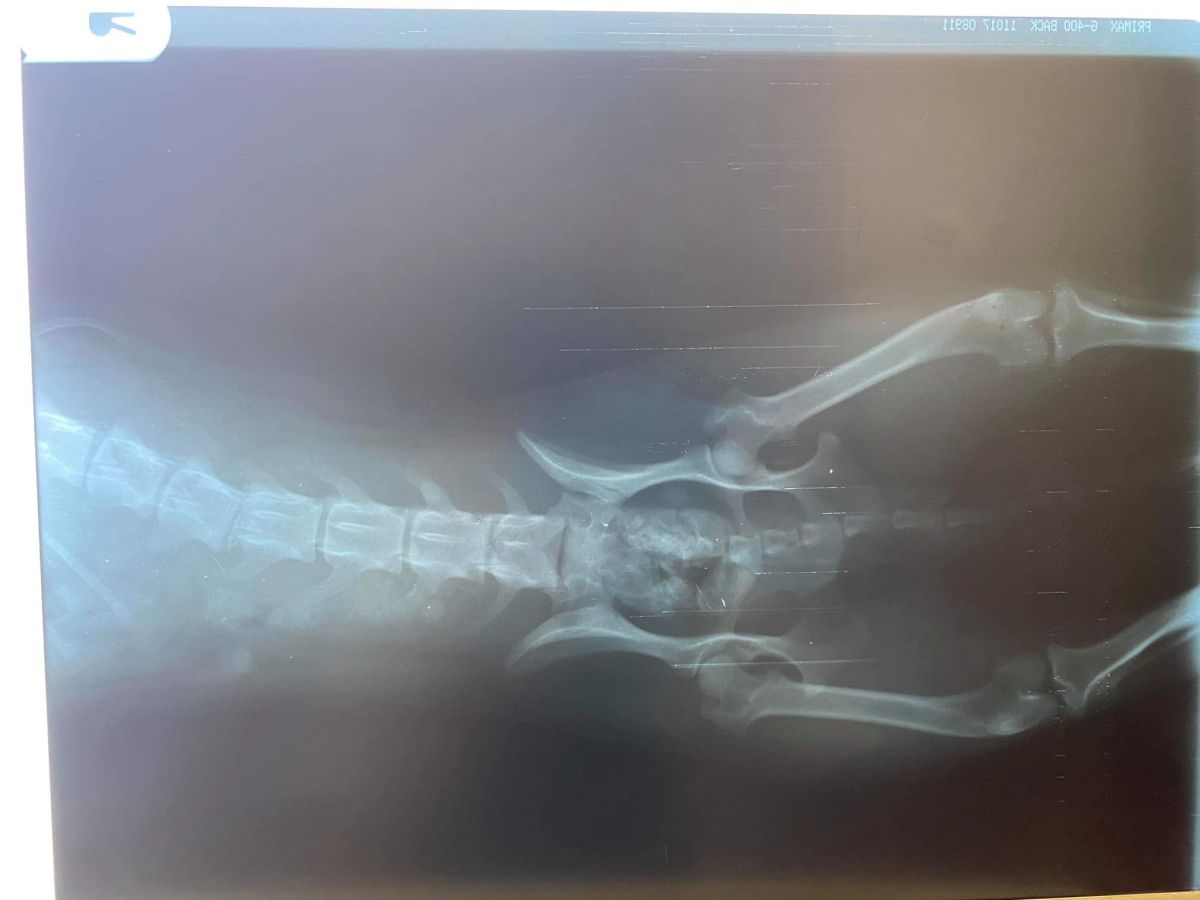

”Am reușit să o stabilizăm iar starea ei este una  bună acum, însă din păcate în urma radiografiilor prezintă o deplasare vertebrală, motiv pentru care momentan este paralizată”,

O intervenție de neuro-chirurgie de fixare a corpurilor vertebrale afectate i-ar da șansa unei vieți normale, să poată să meargă din nou.